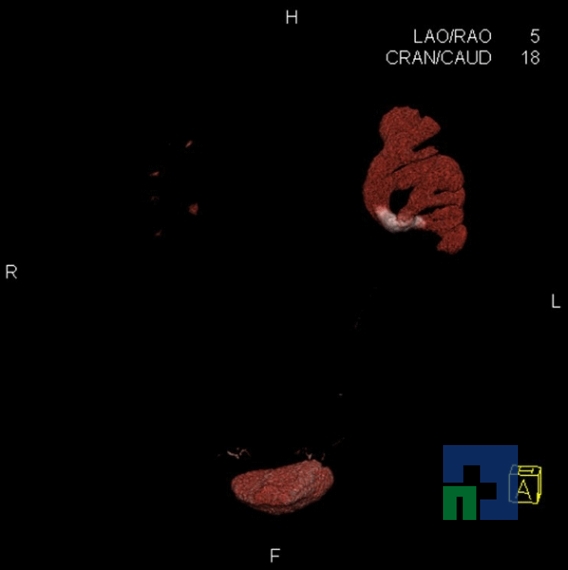

Examinare de rutină cerebrală, nativ și cu substanță de contrast (SDC) pentru diagnosticul:

- Accidentelor vasculare cerebrale ischemice sau hemoragice